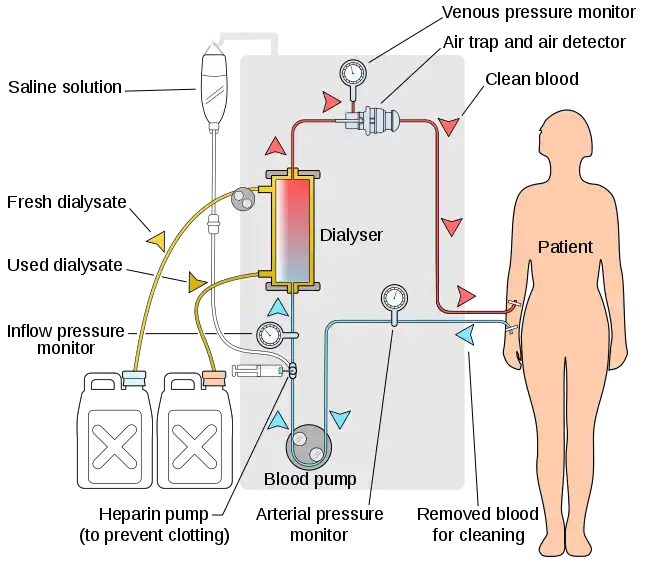

The two main types of dialysis, hemodialysis and peritoneal dialysis, remove wastes and excess water from the blood in different ways.[2] Hemodialysis removes wastes and water by circulating blood outside the body through an external filter, called a dialyzer, that contains a semipermeable membrane. The blood flows in one direction and the dialysate flows in the opposite. The counter-current flow of the blood and dialysate maximizes the concentration gradient of solutes between the blood and dialysate, which helps to remove more urea and creatinine from the blood. The concentrations of solutes normally found in the urine (for example potassium, phosphorus and urea) are undesirably high in the blood, but low or absent in the dialysis solution, and constant replacement of the dialysate ensures that the concentration of undesired solutes is kept low on this side of the membrane. The dialysis solution has levels of minerals like potassium and calcium that are similar to their natural concentration in healthy blood. For another solute, bicarbonate, dialysis solution level is set at a slightly higher level than in normal blood, to encourage the diffusion of bicarbonate into the blood, to act as a pH buffer to neutralize the metabolic acidosis that is often present in these patients. The levels of the components of dialysate are typically prescribed by a nephrologist according to the needs of the individual patient.

In hemodialysis, the patient's blood is pumped through the blood compartment of a dialyzer, exposing it to a partially permeable membrane. The dialyzer is composed of thousands of tiny hollow synthetic fibers. The fiber wall acts as the semipermeable membrane. Blood flows through the fibers, dialysis solution flows around the outside of the fibers, and water and wastes move between these two solutions.[9] The cleansed blood is then returned via the circuit back to the body. Ultrafiltration occurs by increasing the hydrostatic pressure across the dialyzer membrane. This usually is done by applying a negative pressure to the dialysate compartment of the dialyzer. This pressure gradient causes water and dissolved solutes to move from blood to dialysate and allows the removal of several litres of excess fluid during a typical 4-hour treatment. In the United States, hemodialysis treatments are typically given in a dialysis center three times per week (due in the United States to Medicare reimbursement rules); however, as of 2005 over 2,500 people in the United States are dialyzing at home more frequently for various treatment lengths.[10] Studies have demonstrated the clinical benefits of dialyzing 5 to 7 times a week, for 6 to 8 hours. This type of hemodialysis is usually called nocturnal daily hemodialysis and a study has shown it provides a significant improvement in both small and large molecular weight clearance and decreases the need for phosphate binders.[11] These frequent long treatments are often done at home while sleeping, but home dialysis is a flexible modality and schedules can be changed day to day, week to week. In general, studies show that both increased treatment length and frequency are clinically beneficial.[12]